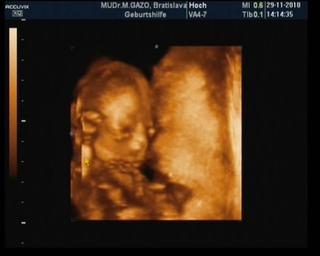

no a boli sme na 3D trosku predcasne, ale som chcela aj vediet ci babenko rastie ked ja chudnem a mojho doktora to nezaujimalo.. no a som si myslela, ze uz sme 20ty tyzden.. ale sme boli 19ty, tak babenko bolo este malicke 200gr (ale moje ma realne este o tyzden menej lebo medzi menzesom a pocatim sme mali 3 tyzdne a nie 2)..

tak zda sa, ze je predsa len o tyzden mensia ako by mala byt, ale verim, ze to sa este dobehne ako bude treba

a pohlavie nemame tiez iste, ale no vyzera to skor na dievcatko